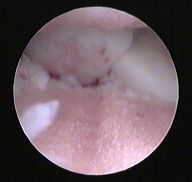

Medial Compartment Disease - MCD lakťového kĺbu

Jedná sa o veľmi obmedzujúci stav lakťa, ktorého príčinou sú pokročilé zmeny chrupavky kĺbu, kde tlak na vnútorný (mediálny) artikulárny povrch podchrupavčitej kosti vyvoláva bolestivosť a nefyziologické vytáčanie nohy psa. Terapia zahŕňa multimodálny management, vrátane artroskopickej liečby a osteotómie ulny, s cieľom znížiť záťaž na mediálny kompartment a zmierniť rozvoj deštruktívnych osteodegeneratívnych zmien.

Vysoká osteotómia ulny je stabilizovaná špeciálnou platničkou, ktorá umožňuje geometrickú korekciu povrchu kĺbu. Vyššia úspešnosť je u mladších psov, u ktorých je viac zachovaná chrupavka vonkajšej strany kĺbu a následne očakávaná väčšia distribúcia záťaže.